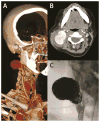

Figures